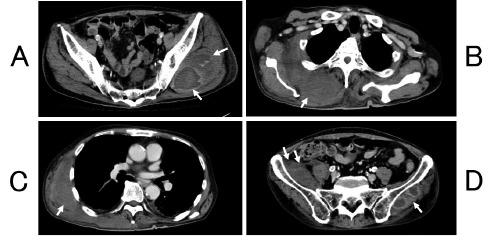

A 74-years-old male who was a smoker and received treatment for hypertension, dyslipidemia, peripheral arterial disease and idiopathic interstitial pneumonia complained of subcutaneous hemorrhage of the right lower thigh. Marked anemia (hemoglobin 5.5 g/dL) and prolonged activated partial thromboplastin time (≥130 seconds) were noted. The factor VIII activity level was reduced to 1.2%, and the factor VIII inhibitor titer was 285.3 BU/mL, a diagnosis of acquired hemophilia A (AHA) was made. Then, hematomas of 5 intra-muscles were recurred. Hemostasis became difficult despite frequent and high-dose administration of recombinant human coagulation factor VIIa (total: 18 days, 305 mg). Hemostasis was achieved by switching to activated prothrombin complex concentrate (for 3 days, 18,000 units), however, cerebral infarction occurred after 36 days. After the frequent administration of bypass hemostatic agents on elderly AHA patients with several risk factors for ischemic stroke, the risk of subsequent thrombotic events may persist for 1 month.

https://cdn.ncbi.nlm.nih.gov/pmc/blobs/03b9/6151351/44a8259255e1/hr-10-3-7453-g001.jpg